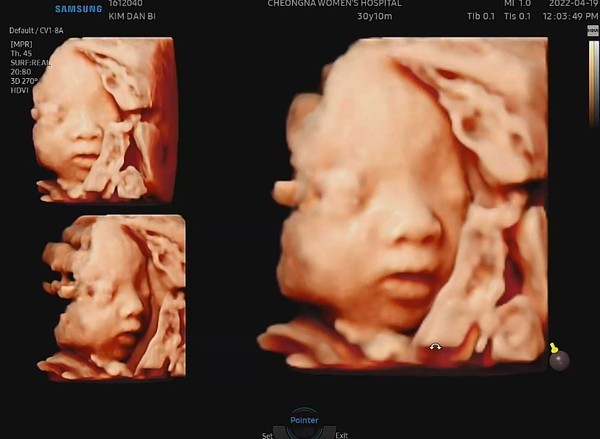

□ 수동적 방법 오직 정보를 얻으려고 초음파를 이용하는 것을 뜻한다. 예를 들면 의사들은 초음파를 이용해 태아의 발달 상태를 관찰한다. 초음파는 종양이나 담석, 심장병을 비롯한 질병의 진단에도 쓰인다. 의사들은 대부분 초음파 검사가 아무런 부작용이 없다고 믿고 있다.

☞초음파트랜스듀서는 초음파를 발생시킨 다음, 반사되어 오는 초음파를 다시 전기펄스로 바꾼다. 반사음의 방향이나 펄스의 세기와 같은 자료를 컴퓨터가 받아 태아의 코와 입술의 영상을 만들어낸다.